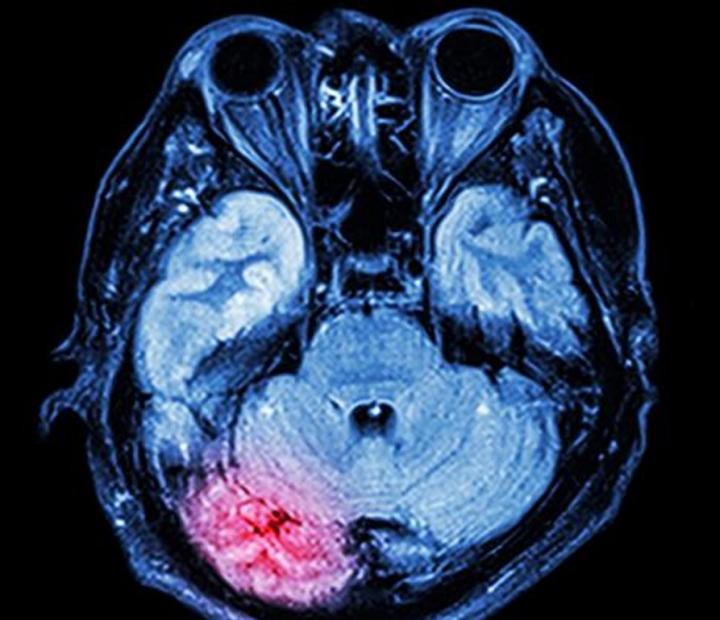

image: The red area shows where the brain is inflamed after concussion.

The link between concussion and neurogenerative diseases is well established, but new research findings could halt the progression of chronic traumatic encephalopathy (CTE) in sportspeople who sustain repeated blows to the head.

CTE is a progressive and fatal brain disease associated with the accumulation of a protein known as hyperphosphorylated tau which affects cognition and behaviour.

The team of researchers from Adelaide, Melbourne and the United States say the brain releases a neurotransmitter called substance P in the event of a head injury, causing abnormal amounts of the tau protein to collect inside neurons.

"Tau protein tangles are a feature of CTE, which reportedly leads to memory problems, confusion, personality changes, aggression, depression and suicidal thinking," Prof Vink says.